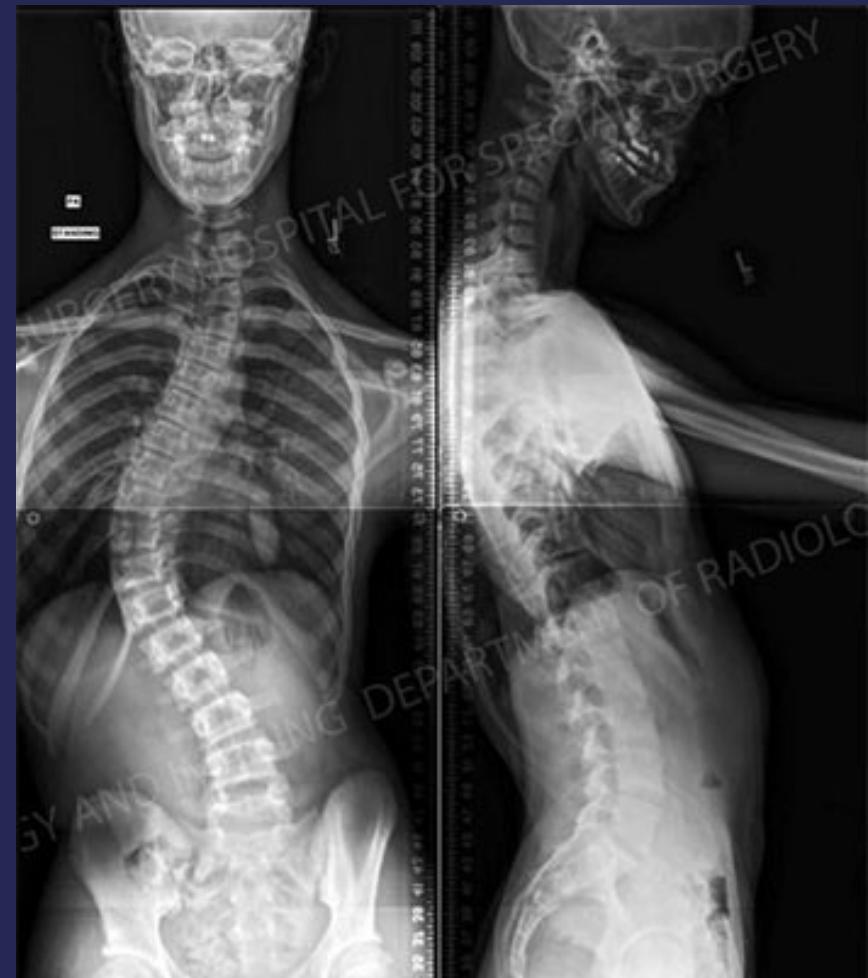

Imaging

- X-ray:

- AP and LAT of entire spine (Cobb angle measurement)

- AP pelvis (Risser grade)

Cobb Angle Measurement

- Select most tilted vertebrae above and below curve apex

- Angle between intersecting lines drawn perpendicular to superior vertebra top and inferior vertebra bottom